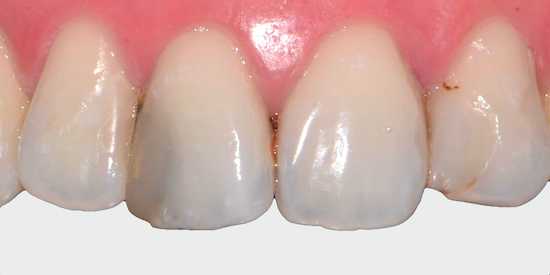

Кариес. Наиболее распространенная причина потемнения зубной эмали. Отличительной особенностью является изменение цвета одного зуба. В редких случаях темнеет несколько соседних зубов. Кариес может проявиться в виде пятна или кариозной полости. Если протекает пришеечная форма кариеса, то темнеют корни зубов (прикорневая зона).

Деминерализация эмали развивается постепенно: сначала структура эмали становится шероховатой и утрачивает естественный блеск, затем появляется меловидное пятно. Оно выглядит так, будто по зубу провели белым мелом.

![Меловидные пятна на эмали [14]](https://probolezny.ru/media/bolezny/demineralizaciya-emali-zubov/melovidnye-pyatna-na-emali-14_s.jpg)

Эмаль зуба становится более пористой, поэтому быстрее изменяет цвет (желтеет и темнеет) под воздействием неблагоприятных факторов. Также повышается чувствительность зубов на раздражители — сладкое и холодное.